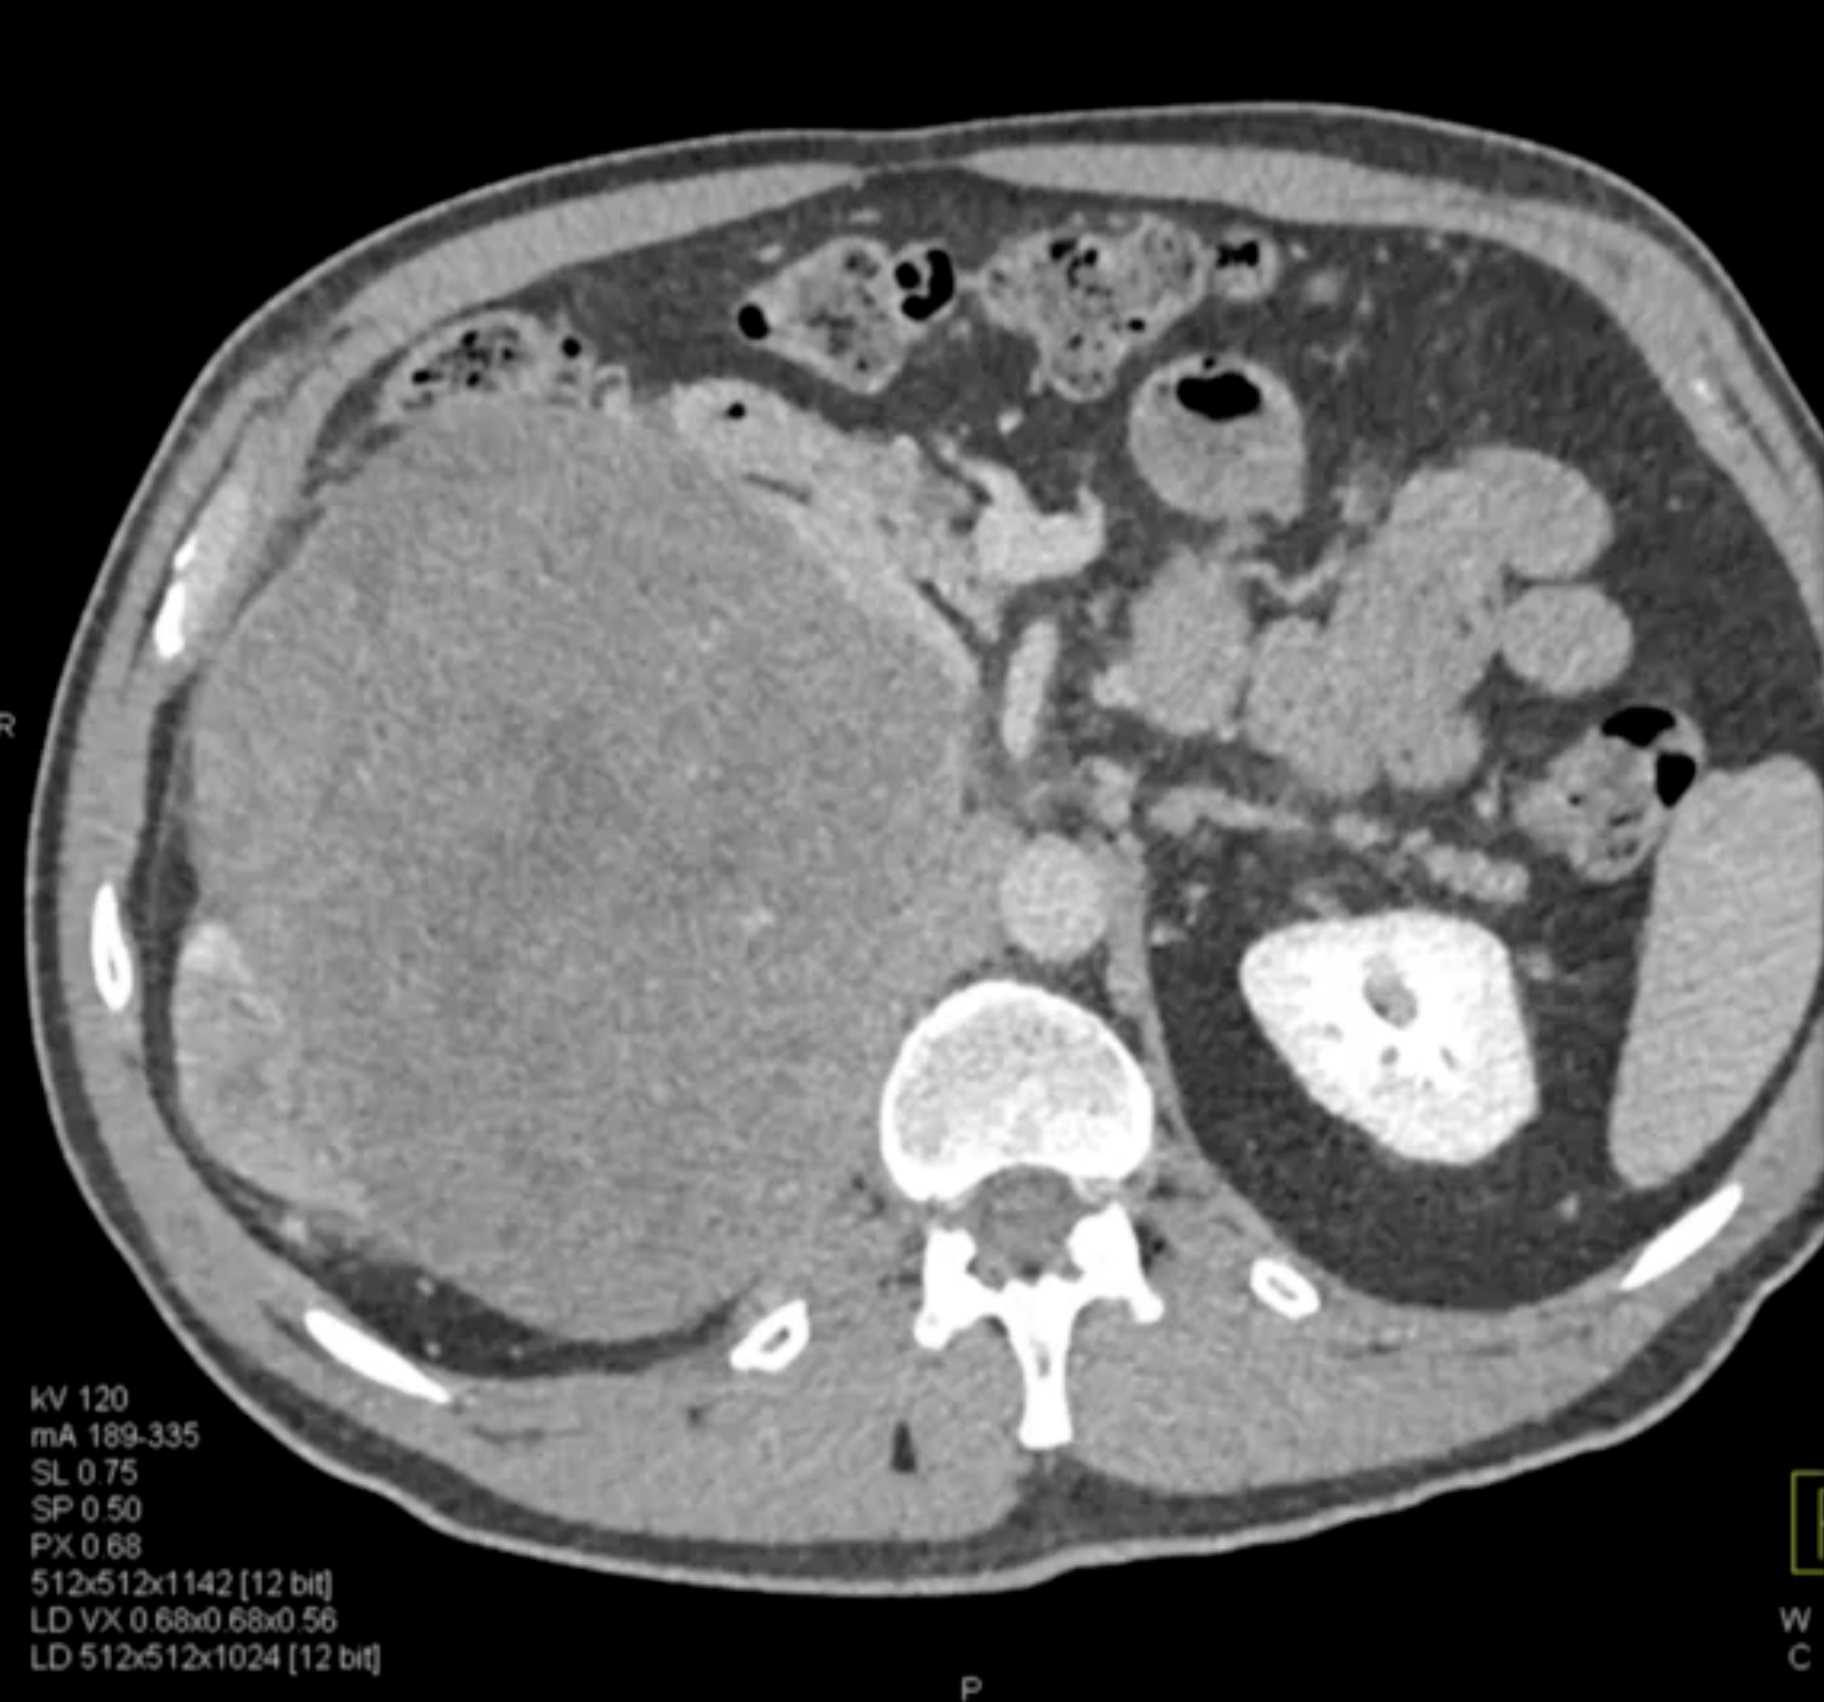

Left Adrenal Metastases from Renal Cell Carcinoma